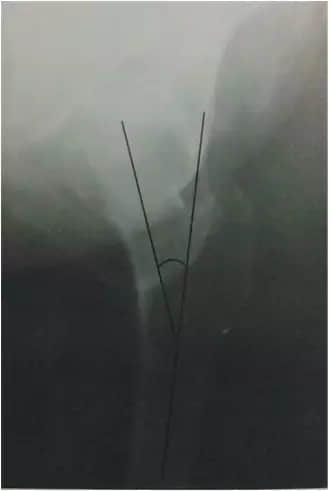

16 Power角

骨盆正位片,过两侧髂前上棘做一水平线,再做股骨颈骨折的延长线而形成的夹角。小于30度为外展型骨折;大至30-90度者为内收型骨折,需手术治疗。

17 Linton角

髋关节正位片,做股骨干纵轴垂线与股骨颈骨折延长线的夹角。小于30度为外展型骨折,易愈合;大至30-90度者为内收型骨折,需手术治疗。